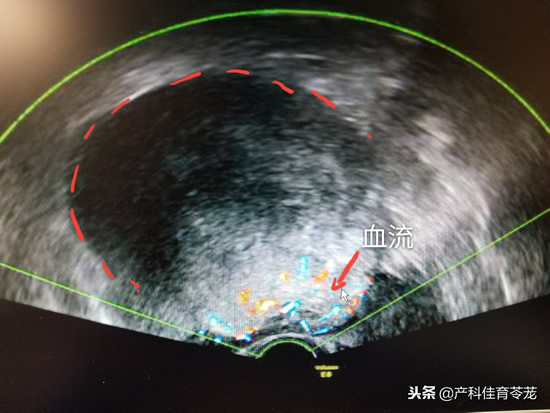

如果发现卵巢有异常,一般是长了肿瘤了,B超会报肿瘤大小,里面的液体是什么样的,形态是不是规则,边缘或者边界是不是清楚,彩色多普勒周边有没有血流,血流是不是丰富。

这种肿瘤里面的成分很复杂,跟周围组织会有粘连,所以B超下的特点是形态多不规则、轮廓模糊、边界不清、壁厚薄不均、内回声强弱不一,呈弥漫性分布的杂乱光点,光团,有出血坏死,囊性变时,可局部形成无回声区,彩色多普勒可见丰富血流信号。常同时合并有腹水。

看到这里,您可能会说,良性肿瘤和恶性肿瘤的B超图像太像了,仔细对比一下,会发现良性的边界更清楚、形态比较规则,里面大部分是液性暗区(黑色区域),而恶性的边界不是很清楚,形态也不是很规则,里面除了液性暗区,还有杂乱的回声(发白的区域),血流相对更丰富。